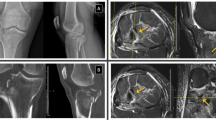

A 43-year-old male elite level ironman triathlete and ultra-marathon runner was referred with an insidious onset of exertional left mid-tibial pain. Prior to the onset of pain, he was conducting his normal weekly training load of 20 h of triathlon training (including swimming, cycling and running a total of 30–40 miles/week). He noticed a mild swelling in the mid part of his shin and some minor discomfort when running. He was reviewed by his GP who performed a radiograph (Fig. 2a). This showed several short linear lucencies within the anterior cortex of the mid-shaft of the tibia, representing incomplete stress fractures. He was subsequently referred to the clinic and was advised to cease running. There were no previous bone stress injuries and no specific metabolic bone risk factors were identified.

(a)HSR72773 Lateral radiograph of the left tibia demonstrating several short linear lucencies within the anterior cortex of the mid-shaft of the tibia, representing incomplete stress fractures (arrows). Sagittal T1 (b) and STIR (c) images of left tibia showing no evidence of marrow oedema or periosteal change. (d) Sagittal CT of left tibia confirming the fracture sites demonstrated on radiographs (arrows)

On examination in clinic, 2 months following the onset of his symptoms, there was no significant tenderness on either border of the left tibia. He was able to fully load the left leg and hopped repetitively without any pain. Subsequent MRI revealed the absence of any bone marrow or muscle abnormalities and no stress fractures were identified (Fig. 2b, c). Computer tomography (CT) confirmed the radiographic findings (Fig. 2d). Following a multi-disciplinary case discussion, a conservative approach was undertaken. After 9 months of conservative management (Table 1), CT confirmed cortical bridging at all fracture sites and he gradually returned to running.

On examination, there were multiple nontender bony ridges in the mid anterior of both tibias. Single leg hop on both legs was not painful. Radiographs showed several short linear lucencies within the anterior cortex of the mid-shaft of both tibias, representing incomplete stress fractures (Fig. 3a). MRI showed no evidence of periosteal reaction or bony oedema (Fig. 3b, c). Subsequent CT confirmed the presence of the fractures (Fig. 3d–f).